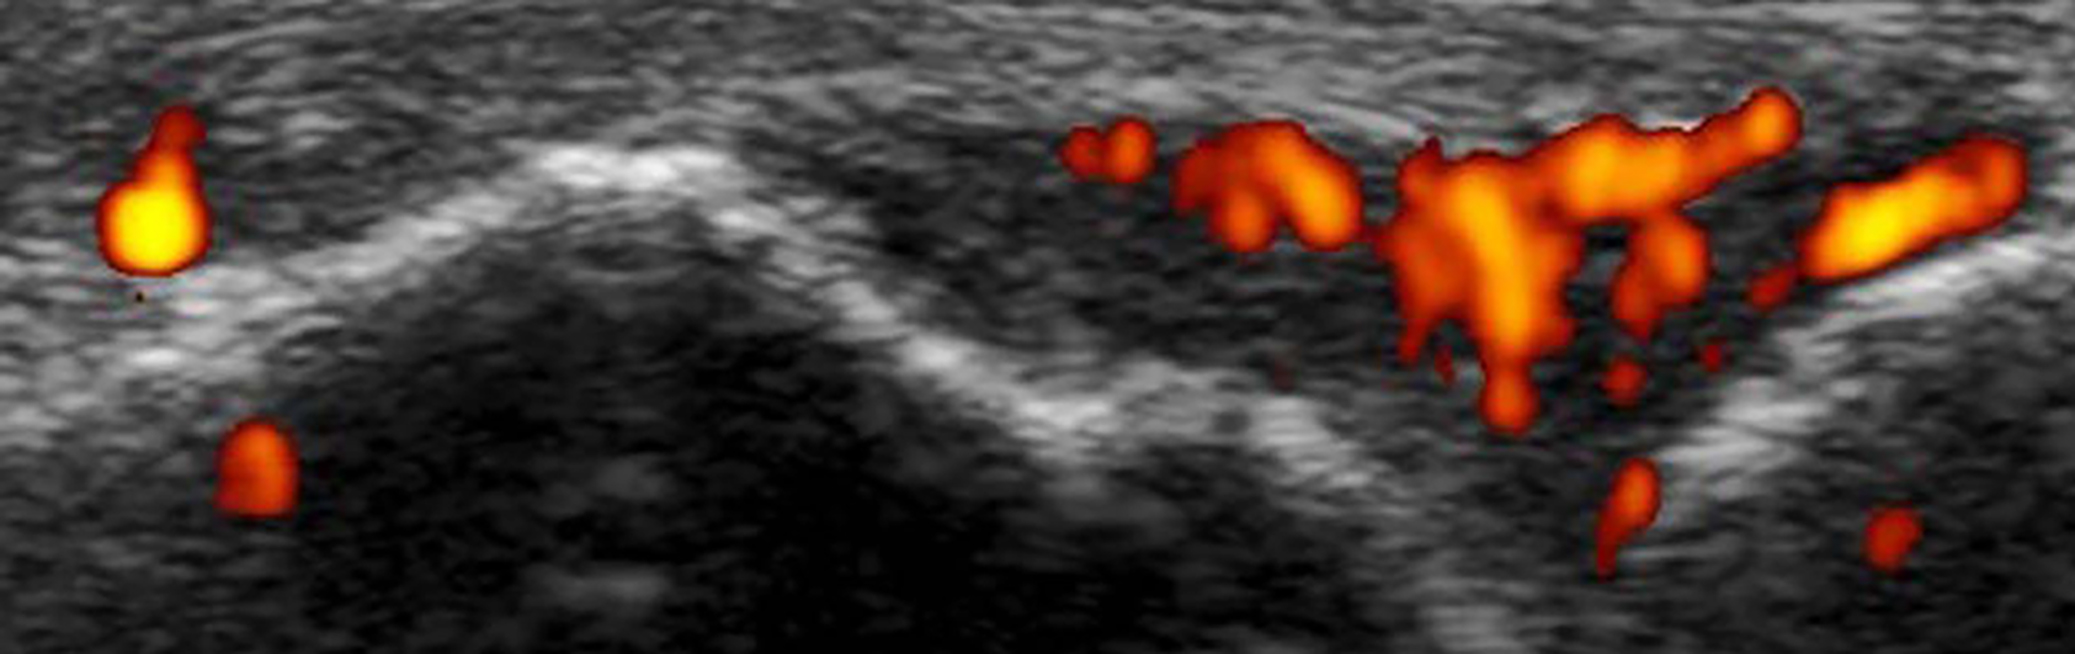

Instead of using surgical techniques such as arthroscopy, we use ultrasound, a completely safe method of seeing inside the joints, to allow us to take tiny, pinhead sized samples from the inner lining of the joint.

Using new research technologies, ultrasound guided biopsy of tissue from the joint has the potential to provide new insights into the mechanisms underlying the development of arthritis and to help us target the right treatment to the right patient.

The ability to take tiny samples out of the joint using ultrasound to guide the procedure is a game-changer for arthritis. We are starting to find markers of different types of arthritis in the tissues during early disease, and we are running studies to show that using tissue from joints can help decide the correct therapy for your arthritis, just as biopsies are used to decide treatment in other conditions.